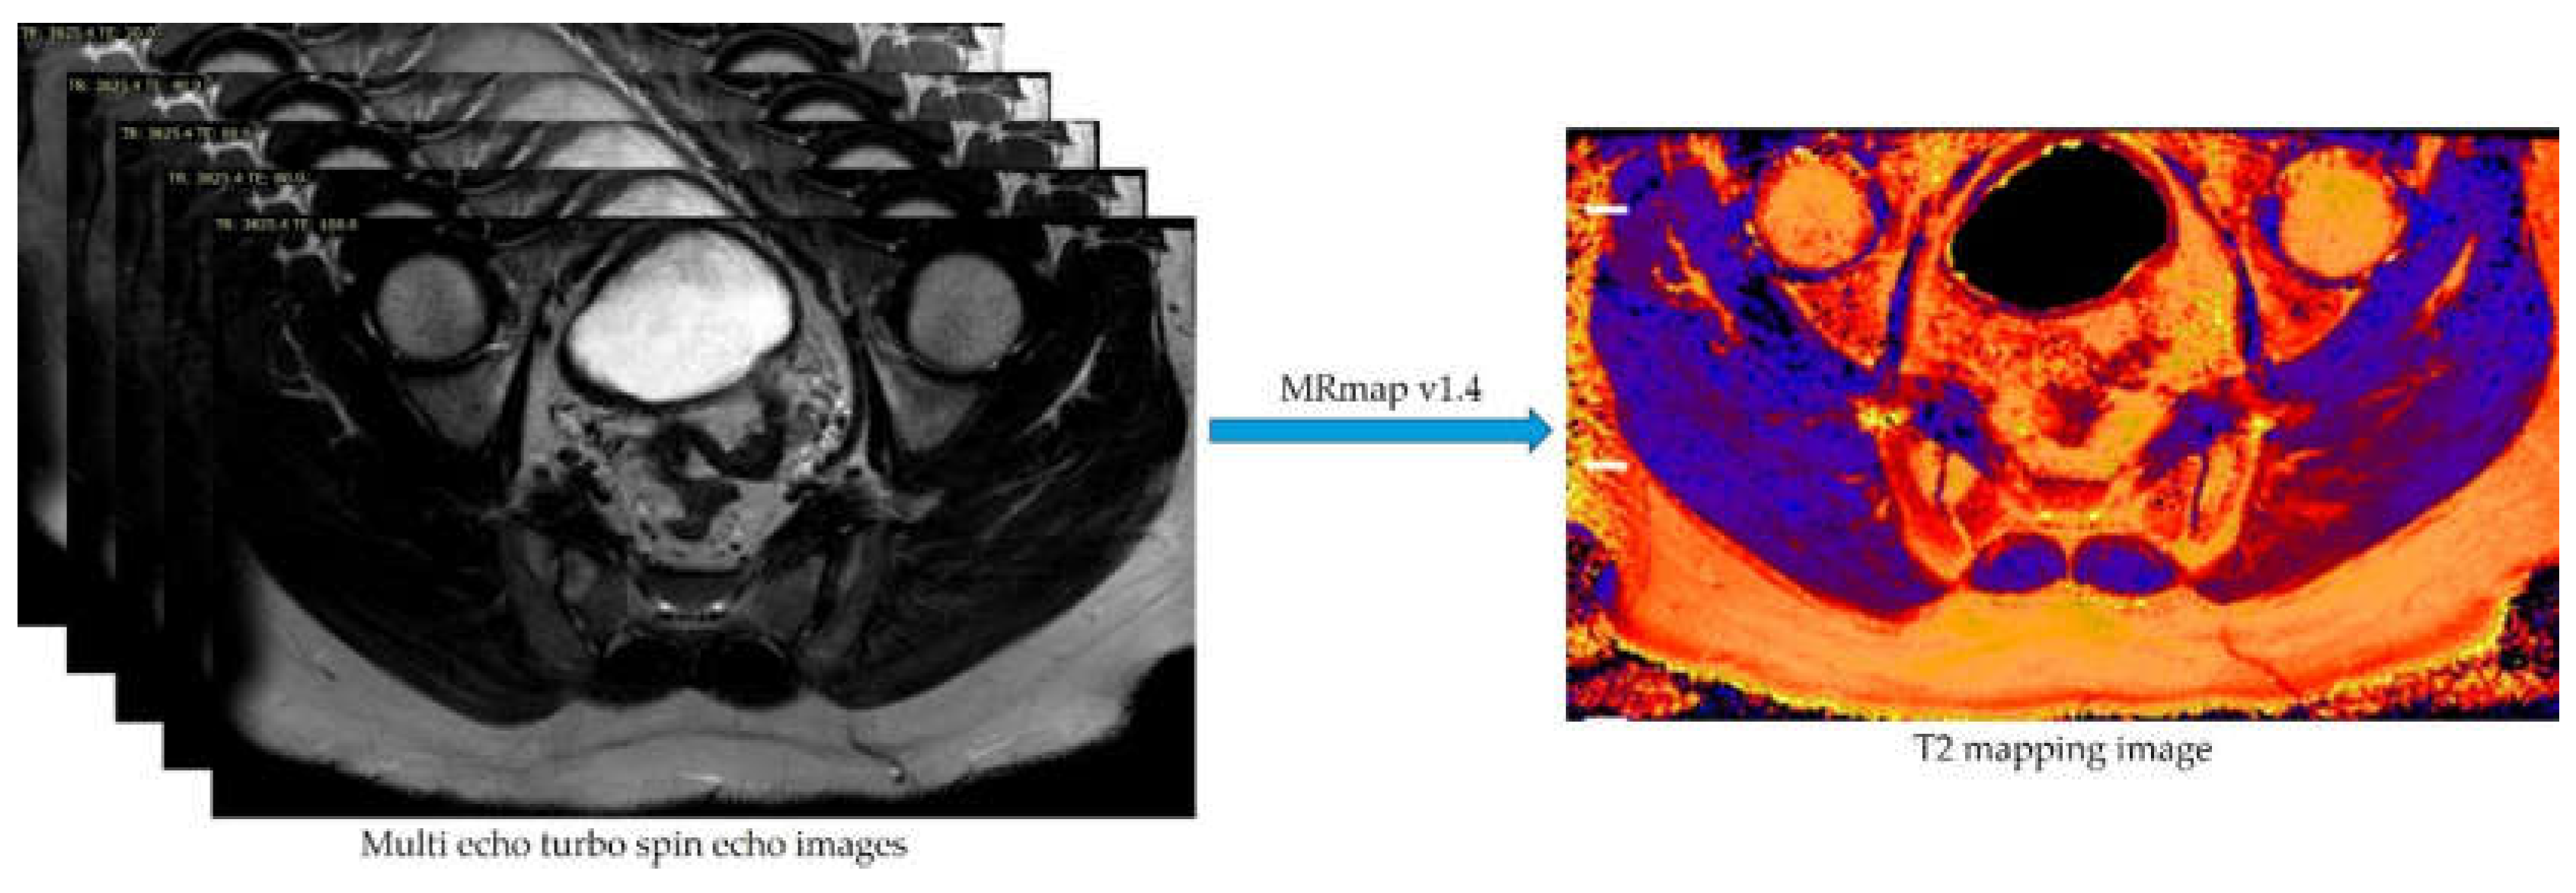

- Messroghli, D.R.; Rudolph, A.; Abdel-Aty, H.; Wassmuth, R.; Kuhne, T.; Dietz, R.; Schulz-Menger, J. An open-source software tool for the generation of relaxation time maps in magnetic resonance imaging. BMC Med Imaging 2010, 10, 16. [Google Scholar] [CrossRef] [PubMed]

- SourceForge. MRmap v1.4. Available online: https://sourceforge.net/p/mrmap/mailman/message/30100362/ (accessed on January, 2021).

| Parameters | Multi-echo TSE |

| Plane | Axial oblique |

| TE (ms) | 20, 40, 60, 80, 100 |

| TR (ms) | 3825 |

| No. of echoes | 5 |

| Echo spacing (ms) | 20 |

| FOV (mm) | 200 |

| Flip angle (°) | 90 |

| No. of signal averages | 1 |

| Slice thickness (mm) | 4 |

| Bandwidth (pixels) | 219 |

| Acquisition matrix | 268x265 |

| Acquisition time | 6.53 min |

| Acquired pixel resolution (mm) | 0.75x0.75 |